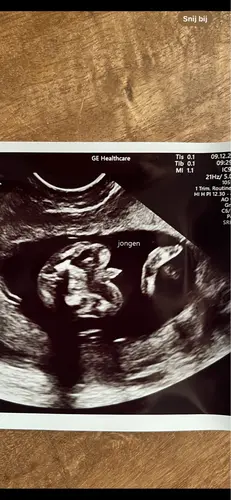

Yes is een jongetje! Had precies dezelfde foto en gisteren te horen gekregen dat het een jongen is. Met 14+5 dagen

Hahaha nou wij willen het geslacht dus niet weten. Maar ik had met de termijnecho 12 weken een inwendige echo. Want het ligt enorm verstopt. Nog nooit gehad (4e zwangerschap!)

Maar inwendig krengen we dit beeld als eerste te zien, 2 benen met een puntje in het midden.. de verloskundige zei er niks over omdat wij het niet willen weten. Maar nu denk ik dus whaha zou het dan toch echt zo zijn!🤣🙈. We hopen stiekem zelf namelijk als gezin wel op een jongen!🥰